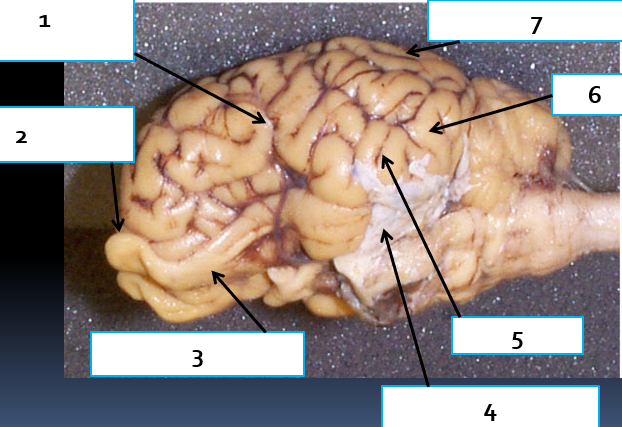

1

cerebral hemisphere, complex reasoning

2

olfactory bulb, houses synapses of olfactory nerve fibers, CN1

3

olfactory tract, carries impulses associated with sense of smell to the brain

4

dura mater, protects the brain

5

sulcus, increase brain surface area

6

gyrus, increase

7

arachnoid mater, protects brain by housing cushioning CSF